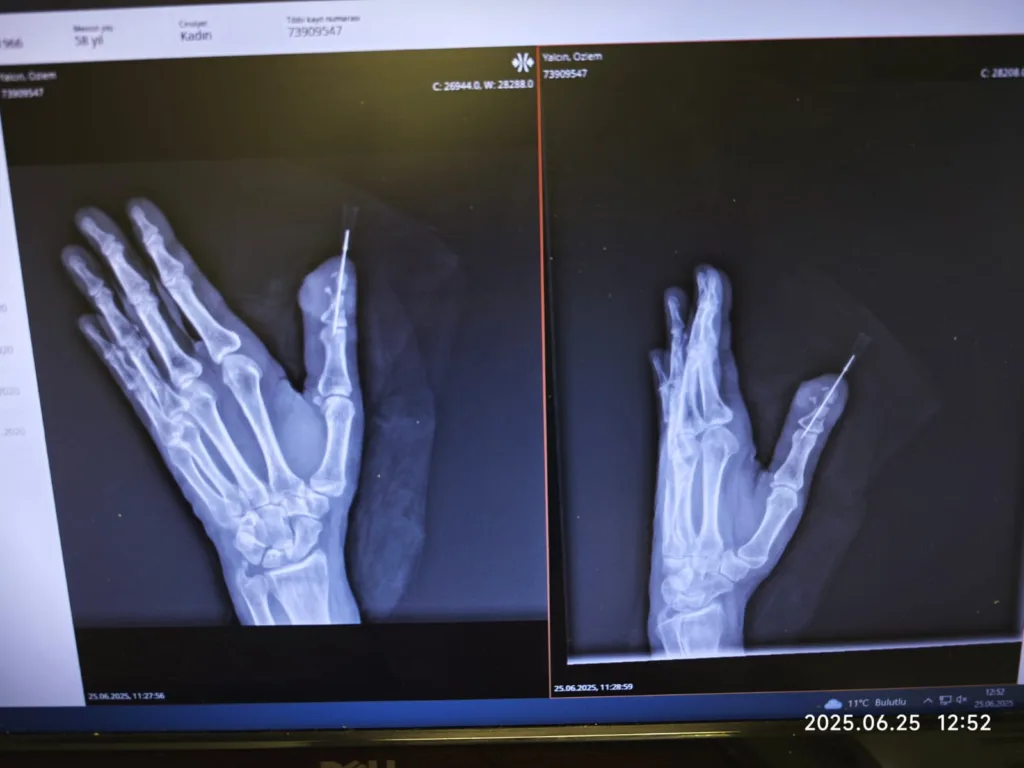

> “Bu tür replantasyon operasyonlarında arter ve ven damarlarının tek tek mikroskop altında yeniden bağlanması gerekir. Ayrıca sinirler ve tendonlar da onarılır. Parmak gibi fonksiyonel ve duyusal değeri yüksek bir organ için bu operasyon çok hassas ve zorludur. Operasyon yaklaşık 4 saat sürdü. Damarlarda kısmi ezilme vardı ama genel yapıları uygundu. Başarıyla damar ve sinir onarımlarını yaptık. Kan dolaşımını tekrar sağladık.”

Operasyon sonrası parmağın kan dolaşımı sağlıklı bir şekilde devam etti. Hastanın tedaviye hızlı ve doğru yanıt vermesi üzerine parmağın kaynaması ve fonksiyonlarının geri gelmesi beklenenden daha iyi seyretti.

> “Bugün hastamızın durumu çok iyi. Parmağın canlılığı tamamen sağlandı. Takip sürecinde herhangi bir dolaşım bozukluğu ya da enfeksiyon gelişmedi. Parmağın tutması, dolaşımının devam etmesi, fonksiyonlarının yeniden kazanılması en önemli göstergeler. Hastamızı bugün taburcu ediyoruz.”